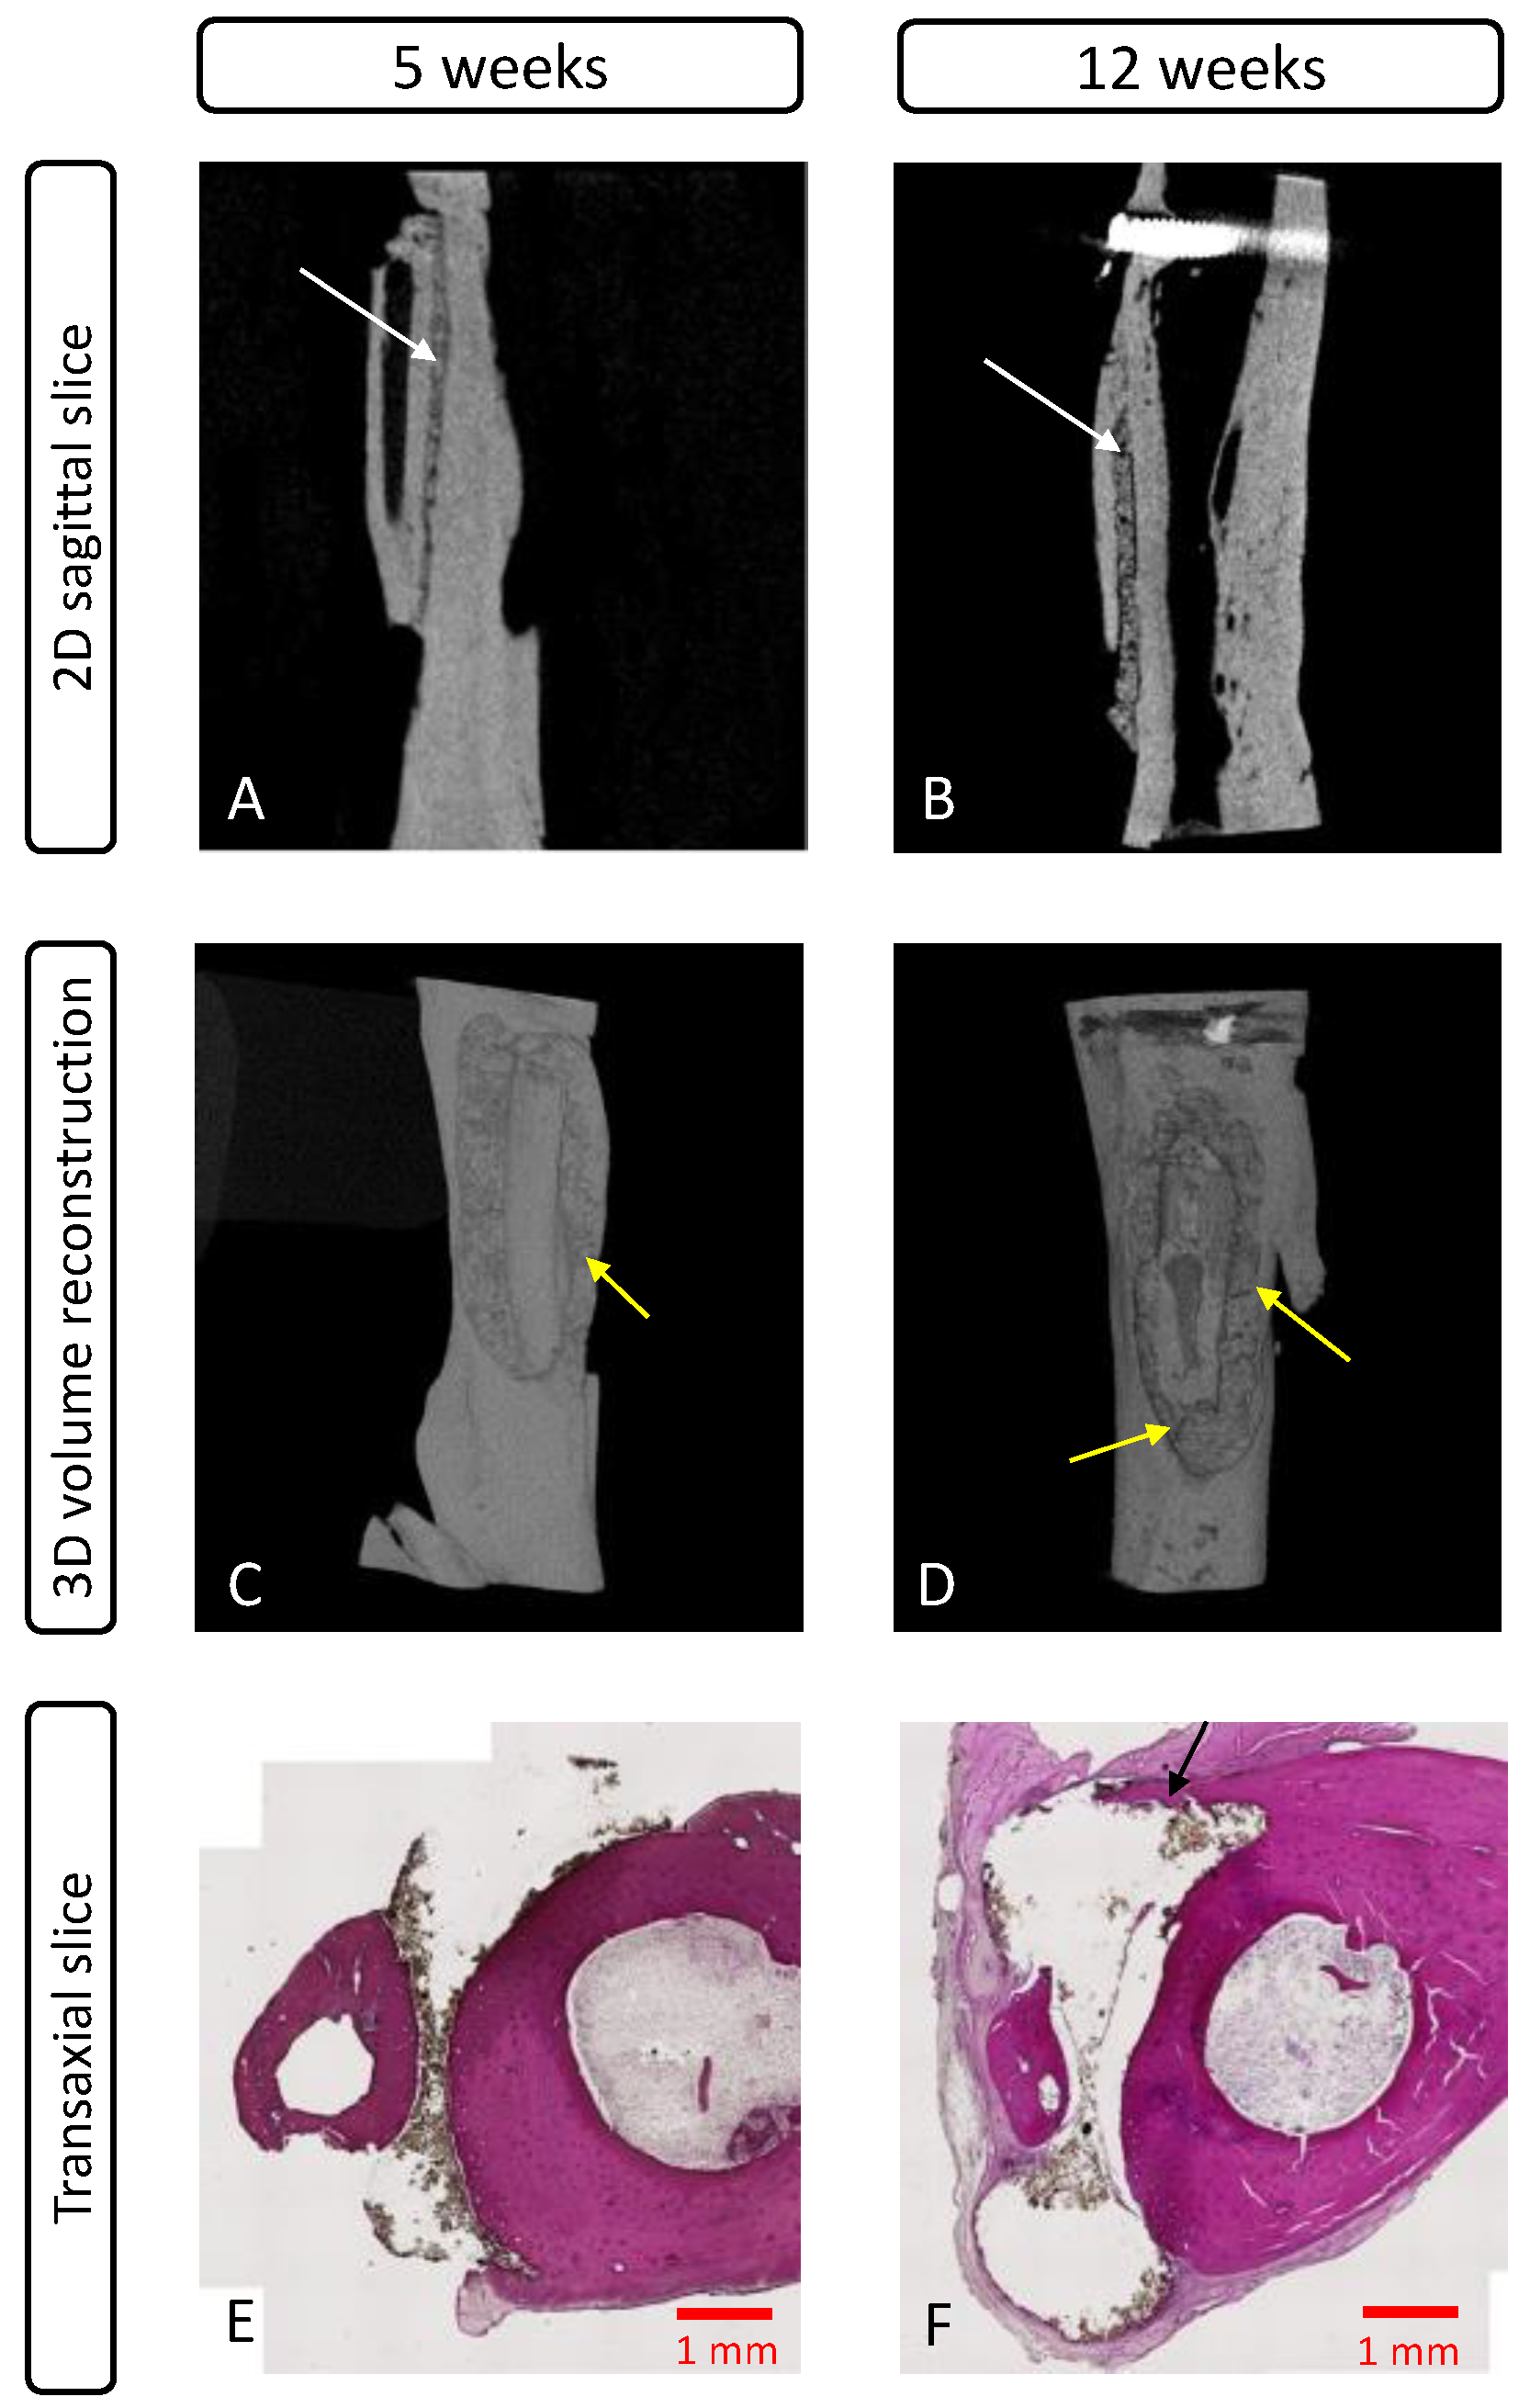

3.4.2. MicroCT Evaluation

3.4.3. Histological Evaluation

| No Fixation | TTCP/OPS-nPDA | |

| 5 weeks | 0% (0/3 sites) | 86% (6/7 sites) |

| 12 weeks | 0% (0/3 sites) | 71% (5/7 sites) |